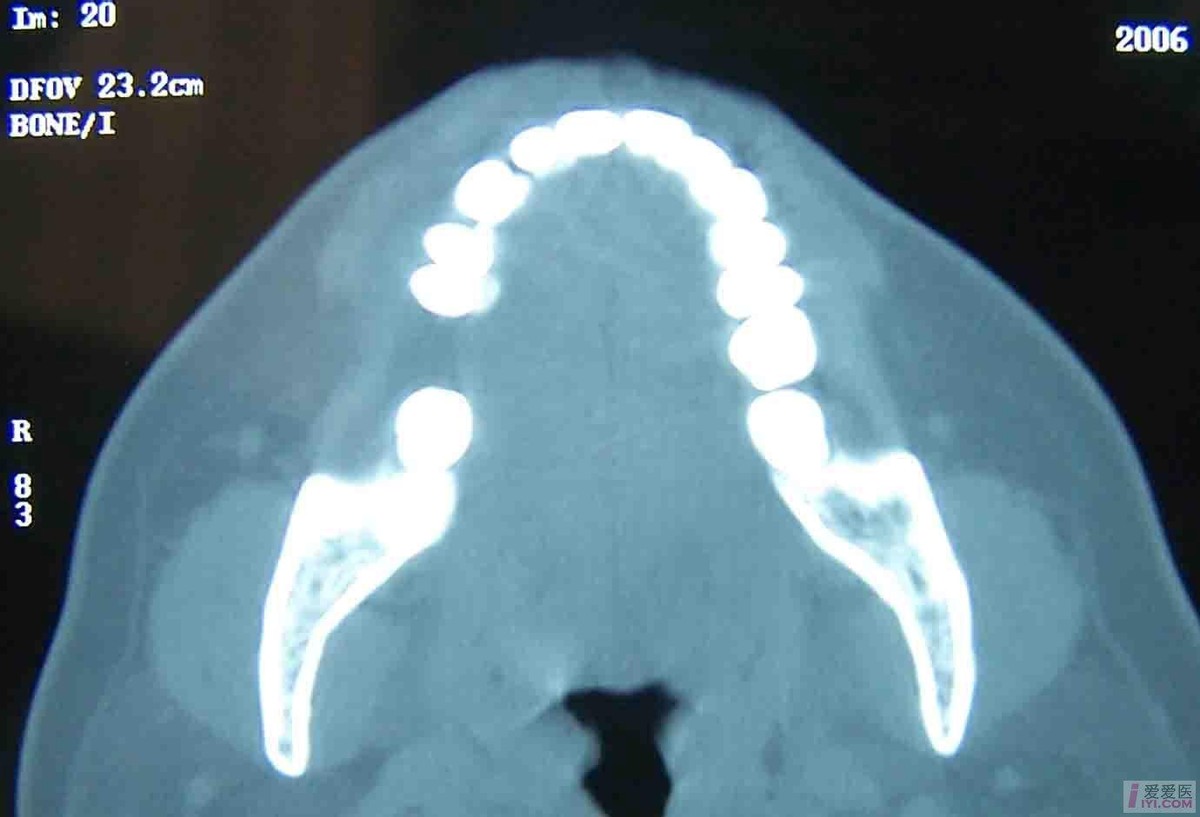

有炎症病史,X线片可见骨质破坏及骨膜增生的修复性改变。临床和X线不能鉴别时,应在手术时作冰冻切片,以排除 中央性颌骨癌 。

X线摄片可见下颌口呈喇叭口状改变,下颌骨扩大。